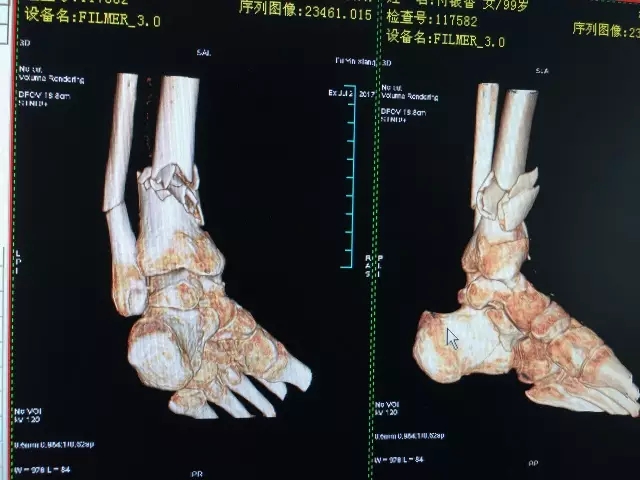

7月26日,99岁高龄的付奶奶不慎被小汽车撞伤,当时感到左下肢疼痛难忍,并有出血,无法站立。随即120将老人送至捕鱼游戏 急诊科,拍片后被诊断为“开放性左胫腓骨粉碎性骨折”,随即转入医院骨科住院治疗。

由于患者是一名年近百岁的老人,骨科主任闵志海反复地对患者身体状况进行了评估,并组织科室医生进行阅片,讨论手术方案。认为如果保守治疗,老人少说也要卧床三个月,而高龄老人最怕卧床不起。大家最后决定尽快为老人手术治疗,术前还邀请了麻醉科医生进行会诊,根据老人的身体状况选择了对患者影响最小的神经阻滞麻醉。